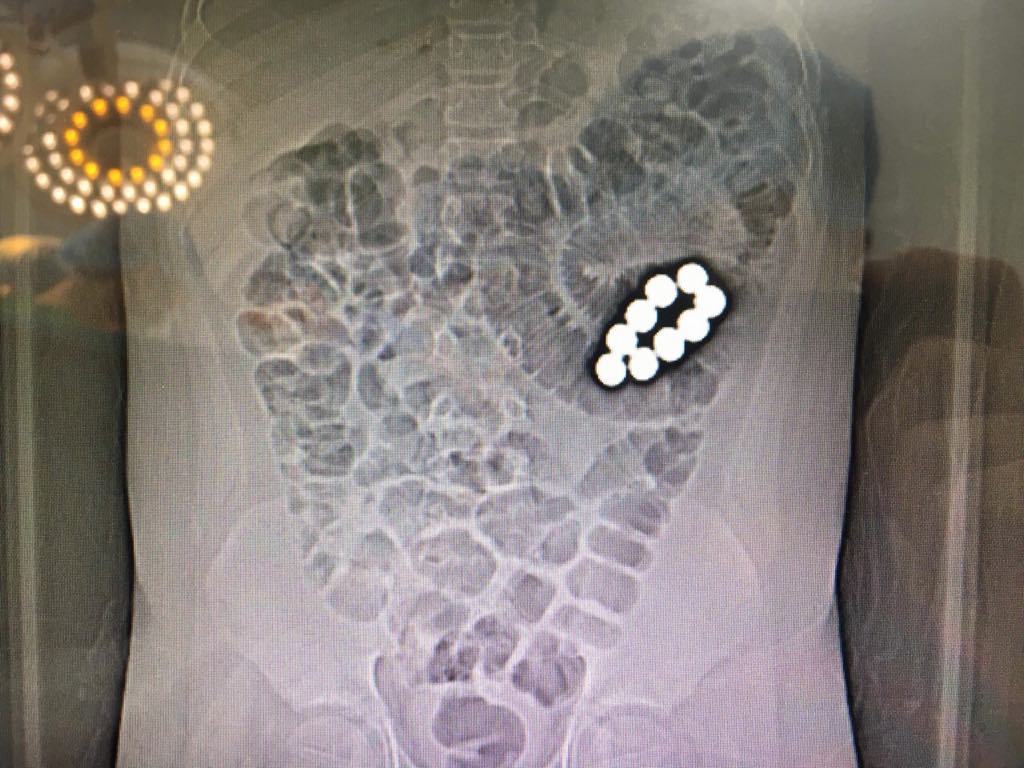

Từ các kết quả xét nghiệm, bác sĩ xác định có dị vật là 9 viên bi nam châm trong ruột non bệnh nhi. 9 viên bi nằm ở 2 khoang ruột khác nhau. Một khoang chứa 7 viên và khoang còn lại chứa 2 viên.

Hai nhóm bi nam châm hút 2 đoạn ruột lại với nhau gây tắc ruột hoàn toàn và dẫn tới hoại tử ruột. Bé được chỉ định phẫu thuật khẩn cấp.

Trải qua ca mổ 3 giờ, các bác sĩ phải cắt 40 cm ruột non để lấy 9 viên bi ra, đồng thời loại bỏ phần ruột bị hoạt tử, trước khi khâu nối lại.

| Hình ảnh chụp phim 9 viên bi nam châm trong ruột non bệnh nhi |